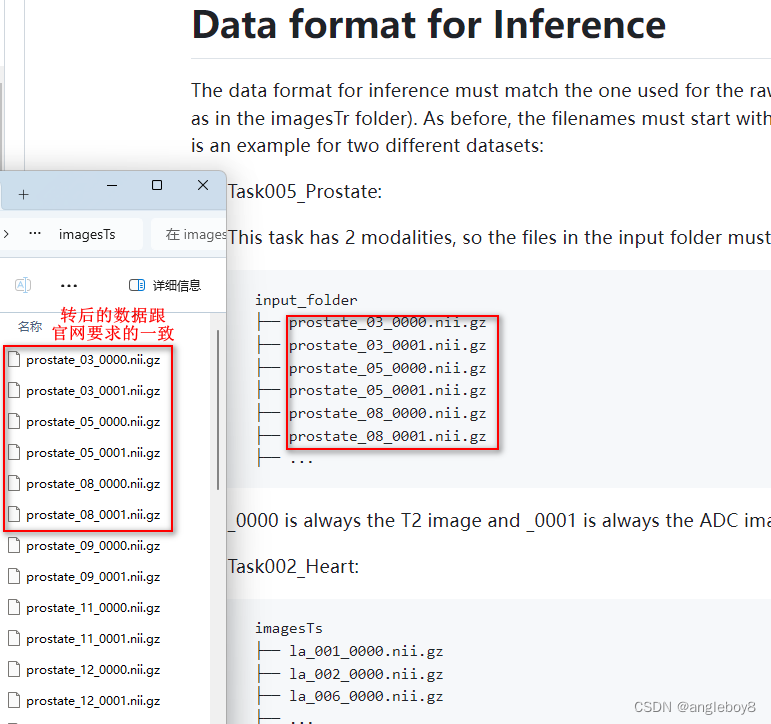

2.开始准备推理的数据,注意它的格式要求,开始体验一下如何用官网模型进行infer使用:

Task005_Prostate

Prostate Segmentation.

Segmentation targets are peripheral and central zone,

Input modalities are 0: T2, 1: ADC.

以imagesTs为例: